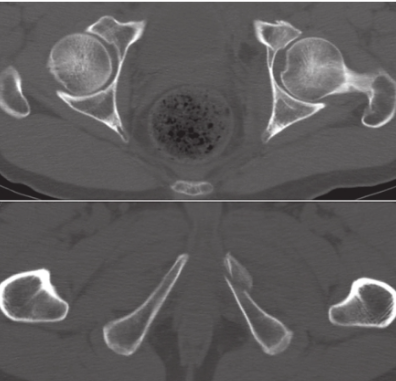

简单骨折:

(1)后壁骨折:CT臼顶层面提示负重区后上缘的粉碎骨折,臼中部层面可显示臼后缘骨折合并缺损。臼中部层面可显示臼后缘骨折合并缺损。

(2)后柱骨折:CT臼顶层面显示骨折线呈冠状方向,在臼中部和坐骨结节层面则分别显示方形区和坐骨结节有骨折,而CT其他层面无骨折。

(3)前壁骨折:臼中部层面可显示髋臼前缘骨折,其他层面无骨折。

(4)前柱骨折:CT相关层面可分别显示髂前上棘、方形区和耻骨支骨折,与前壁骨折比较,前柱骨折的骨折线起点更高(在髂前上棘以上),走行方向更靠近髋臼中心。

(5)横形骨折:CT髋顶稍下层面可显示骨折,在髂前上棘至臼顶及臼窝以下平面均无骨折表现,但通常横形骨折多伴有髋臼下部及股骨头向内移位。

复杂骨折:

(1)双柱骨折:CT臼顶层面显示冠状面骨折,臼中部层面显示方形区骨折,在耻骨、坐骨结节和髂嵴层面分别显示耻骨支、坐骨结节和髂骨骨折。

(2)横形伴后壁骨折:CT臼顶层面显示骨折线呈矢状,臼中部层面内侧方形区无骨折,此为特征性横形骨折表现,矢状骨折是由于远、近骨折段发生前后移位所致。合并后壁骨折者尚显示后壁骨折的CT表现。

(3) T形骨折:CT除有臼顶层面矢状骨折的横形骨折外,尚有方形区和坐骨支骨折的表现(图6)。

图6 CT平扫,更清楚地显示左侧髋臼前柱骨折

(4)后柱伴后壁骨折:CT在臼顶区可见冠状面骨折和后外侧缘骨折(图7),后者提示骨折累及负重区,在臼中部层面可见臼后缘和方形区骨折,在坐骨结节层面可见坐骨结节骨折,其他层面无骨折。

图7 左髋臼后柱骨折伴后壁骨折CT平扫,示左髋臼后柱骨折伴后壁骨折,骨折分离移位